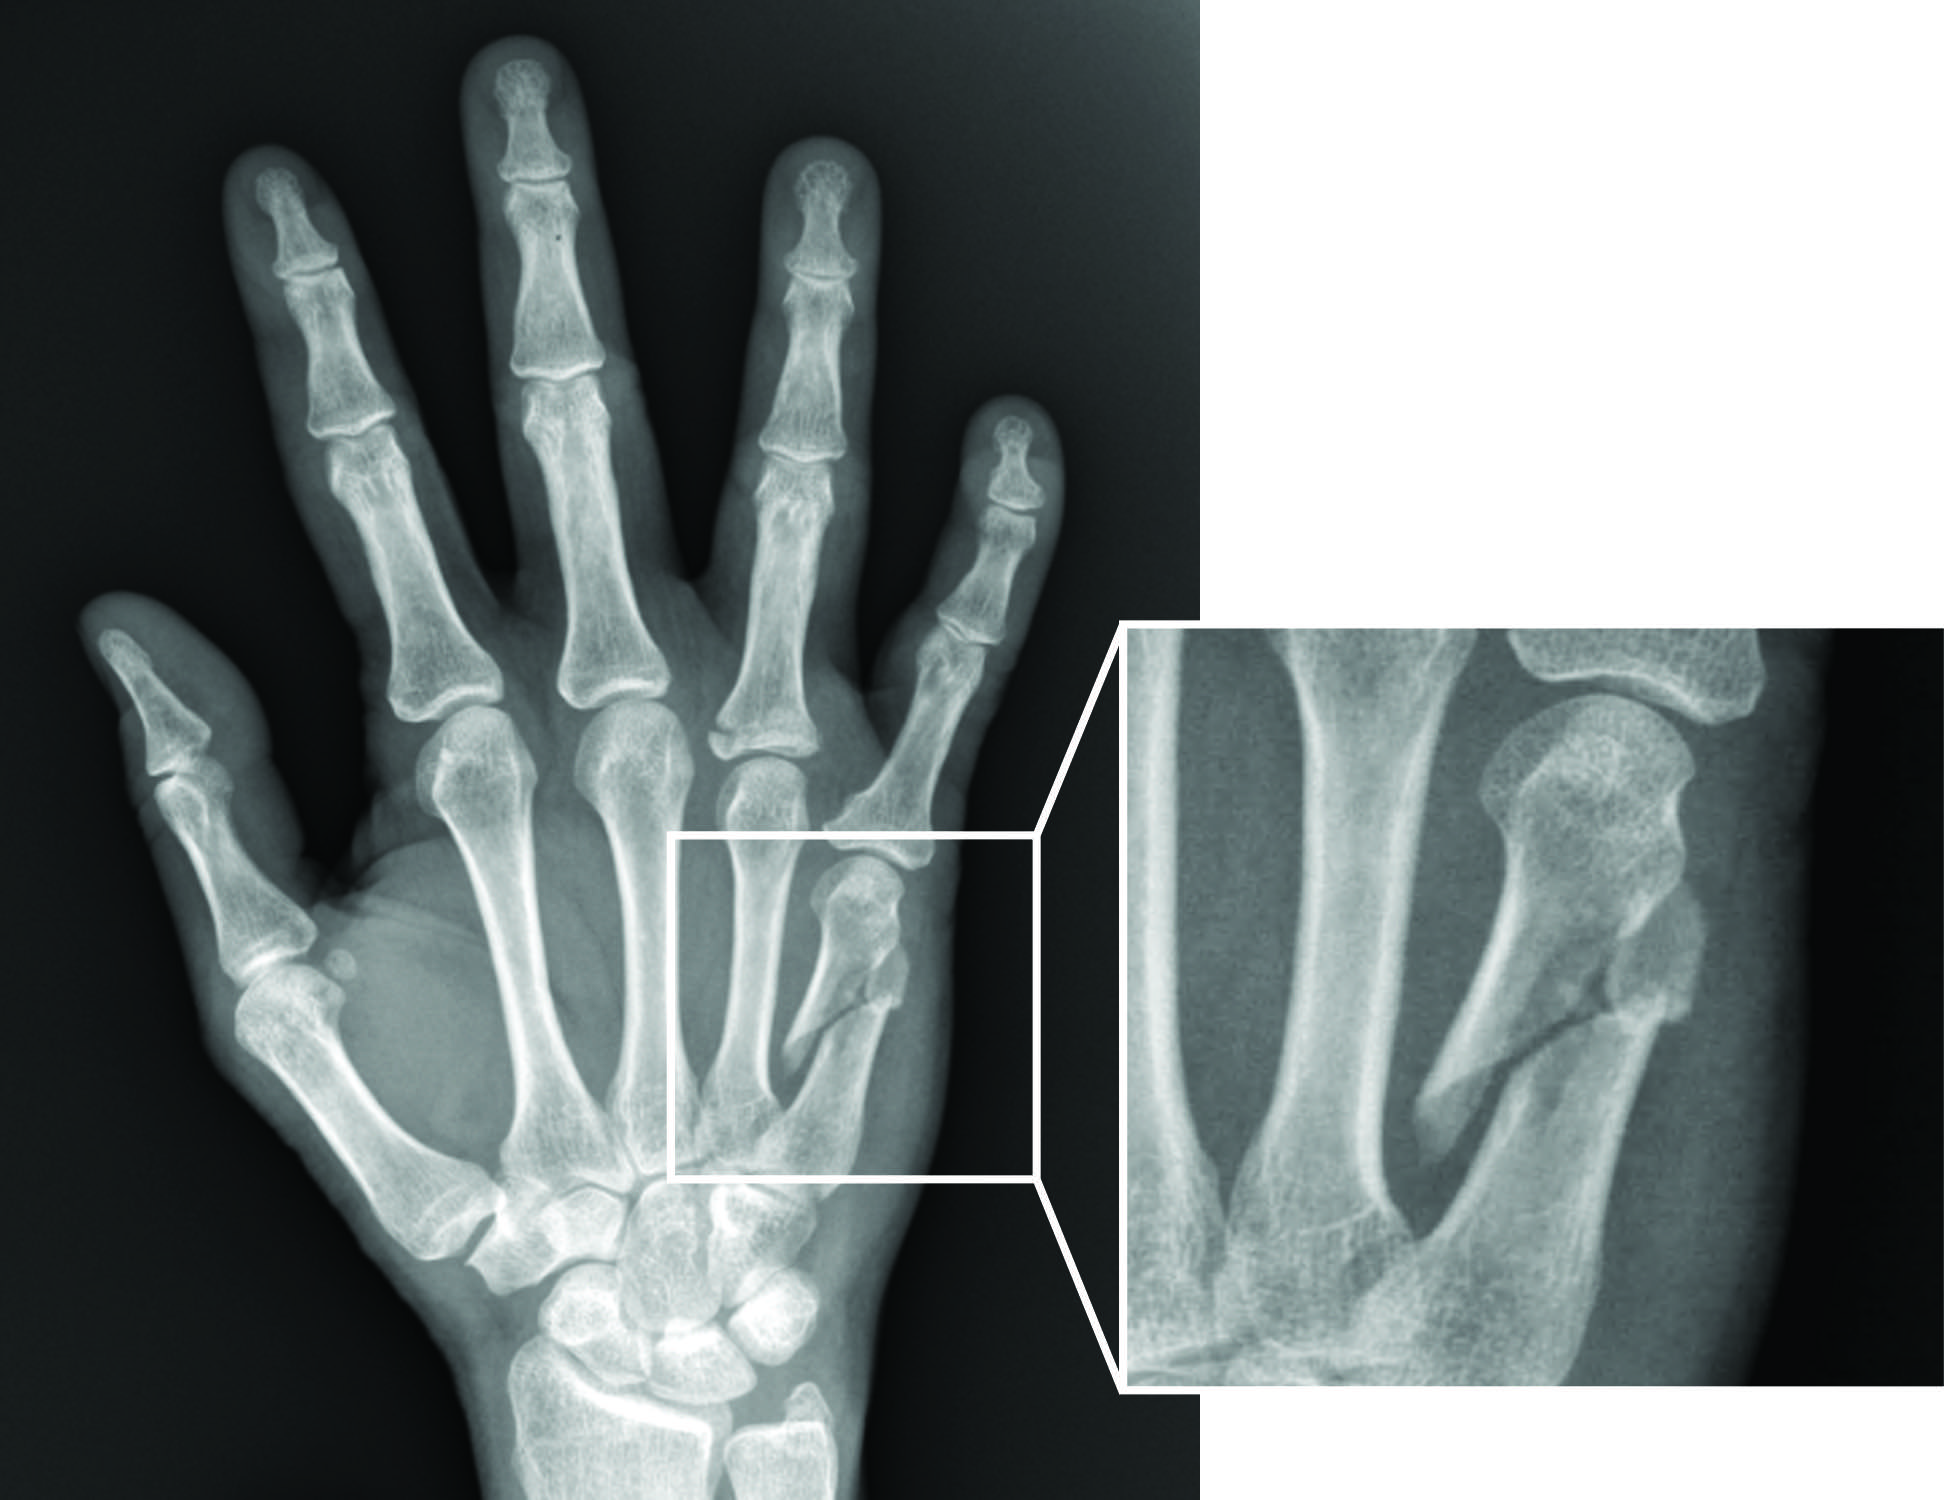

colorized xray of the hand showing a fracture of the 5th finger Stock Photo 31453279 Alamy What Does A Broken Palm Look Like a broken hand happens when one or more bones in your hand break as a result of an accident, fall, or contact sports. look for fracture symptoms like. You’ll probably be able to see. what does a broken hand look like? broken bones most often result from a direct blow to the hand or a fall. What Does A Broken Palm Look Like.